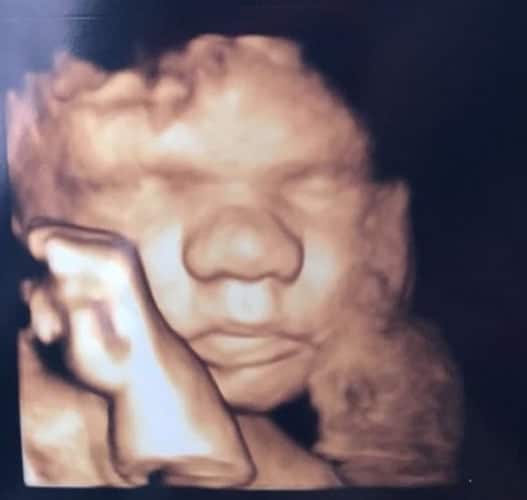

Im dritten Trimester der Schwangerschaft ist das Baby so groß, dass es nicht mehr komplett auf ein Ultraschallbild passt. Nun kann man wunderbare 3D-Ultraschalle des Gesichts machen. In diesem Semester nehmen die Babys nochmal rasant zu und wer Glück hat, kann auf seinem Ultraschall schon erste Gesichtszüge erkennen.

Wer sich jedoch erhofft Gesichtszüge zu erkennen, der wird oft enttäuscht. Zwar kann man beim 3D-Ultraschall schon eine Menge sehen, aber das umgebende Fruchtwasser sorgt in den allermeisten Fällen für starke Störungen.